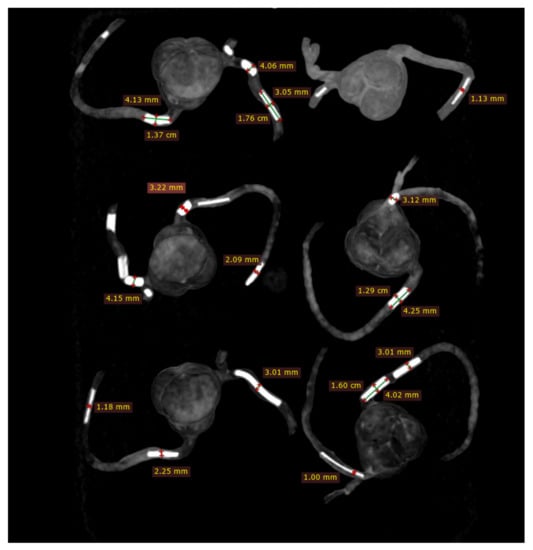

2.4. 2D and 3D Image Reconstruction and Assessment

CCTA images in DICOM format were transferred to a separate workstation for image processing and analysis using RadiAnt DICOM viewer 2020.1.1 (Medixant, Poznan, Poland). Two-dimensional axial images were reconstructed into MIP and 3D volume rendering (VR) views for visualisation of calcified plaques and measurements of plaque dimensions. For VR views, we first used a wide window width (window width and window level: 1250 and 250) to allow visualisation of plaque and coronary lumen. Then, we narrowed the window width (window width and window level: 1050 and 210) to focus on visualisation of the calcified plaques. Measurements of plaque diameter and length were performed on MIP and VR images (wide and narrow window widths), with the results compared to those from the actual sizes of these plaques and any significant differences determined. Measurements were conducted by an assessor (with more than 15 years of experience in cardiac CT imaging) and performed three times at different locations of each plaque with the mean values used as the final ones for comparisons. Figure 5 shows an example of measuring these plaques based on the MIP images, while Figure 6 displays measurements based on two VR views with the use of wide and narrow window widths. According to Society of Cardiovascular Computed Tomography (SCCT) guidelines, although multiplanar reformation is preferred to delineate the plaque morphology and coronary lumen changes, MIP images are useful for identifying artifacts, as well as the presence and position of the coronary lesions, while VR images are useful for demonstrating spatial relationships between coronary lesions and vessels []. As our purpose of this study was to focus on the blooming artifacts associated with heavy calcifications in the coronary arteries instead of assessing lumen stenosis, we compared MIP with VR visualisation tools in this experiment.

Figure 6.

Measurement of plaque dimensions on 3D volume rendering images with the use of different windowing. (A) Measurements of plaque dimensions on wide window width (window width and window level: 1250 and 250). (B) Measurement of plaque dimensions at the same plaque locations with narrow window width (window width and window level: 1050 and 210).

Figure 8 demonstrates coronal and oblique MIP images showing these calcified plaques in the coronary artery models, while Figure 9 presents VR images with window width changed. These 2D and 3D images clearly demonstrate the calcified plaques in the coronary arteries.